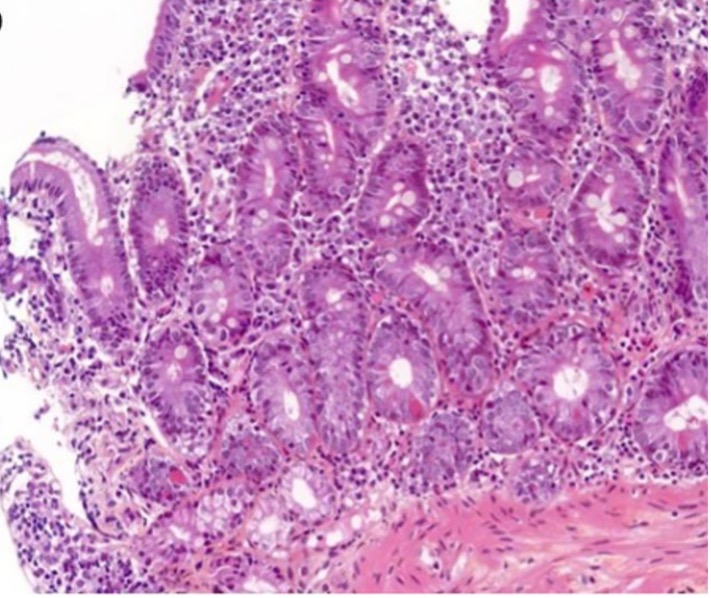

Les atteintes digestives sont parmi les plus fréquentes, en particulier sous anti-CTLA-4 ou traitement combiné 1. Elles peuvent atteindre toutes les parties du système digestif.

Selon le type d’ICI utilisé, les lésions observées seront légèrement différentes 2-6 :

• Lésions de colites aiguës actives à polynucléaires neutrophiles avec une atteinte focale ou diffuse et éventuellement une iléite associée ;

• Colites microscopiques, lymphocytaires et à collagène, qui peuvent être associées à des lésions de colites actives (surtout sous anti-PD-1/PD-L1) ;

• Colites granulomateuses (surtout sous anti-CTLA-4) ;

• Signes de chronicité de plus en plus décrits, caractérisés par un certain degré de distorsion des cryptes, un infiltrat lymphoplasmocytaire basal, une augmentation des cellules de Paneth.

Les lésions histologiques des colites aiguës actives associent un infiltrat inflammatoire polymorphe du chorion, des ulcérations/érosions du revêtement de surface, des exocytoses à polynucléaires neutrophiles responsables de lésions d’abcès cryptiques et éventuellement des granulomes épithélioïdes 2. En immunomarquage, l’infiltrat immun est majoritairement constitué de cellules CD8+ et de Treg+ (sous anti-PD-1/PDL-1) et de CD4+ (sous anti-CTLA-4).

En cas de colites microscopiques lymphocytaires, l’infiltration lymphocytaire intra-épithéliale touche le revêtement de surface mais aussi les cryptes 3, 5.

[Figure 2]

Histologies de colites aiguës actives